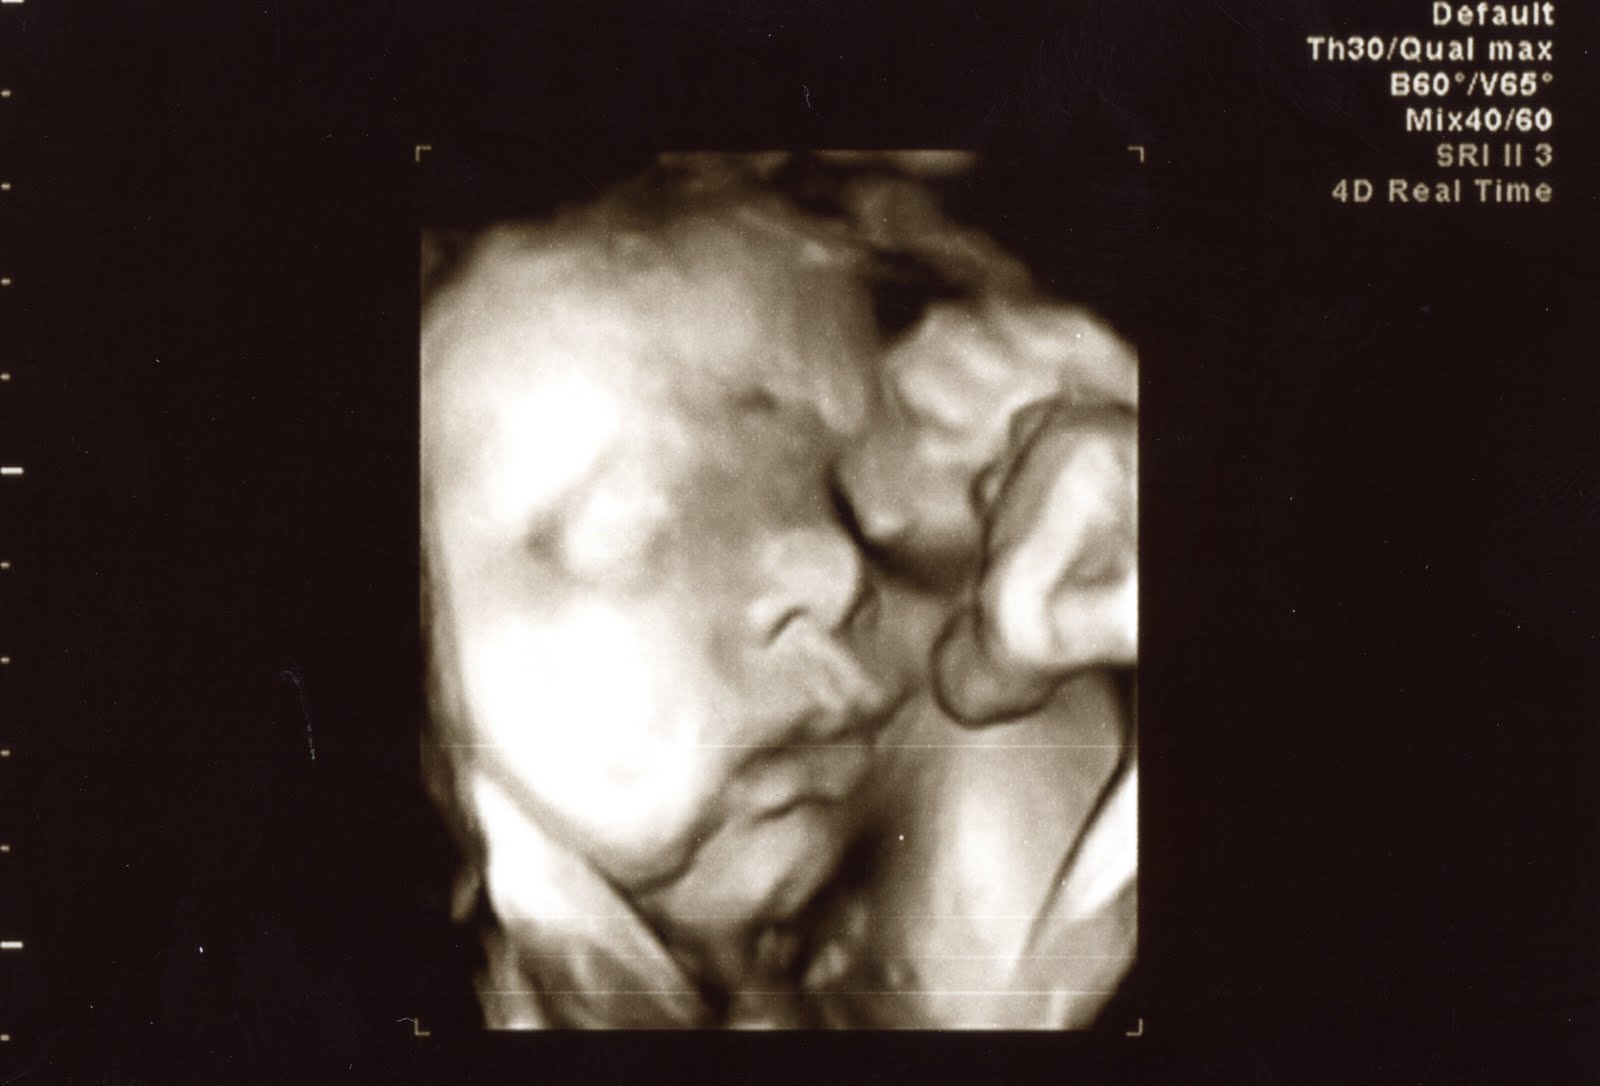

| 33 weeks 1 day, and yes that is a hand and a foot in front of his face! |

| 33 weeks 1 day, looks like he is ready to go back to sleep! |

Next they took me for my biophysical profile, which is another part of my weekly visit. The non-stress test is actually part of the biophysical profile, but I did that part first today. The rest of the profile involves an ultrasound that measures amniotic fluid, heart rate, breathing movements, and activity. Since baby was awake, it took less than 5 minutes to get what we needed. And then the sonographer was nice enough to snap some pictures of baby!